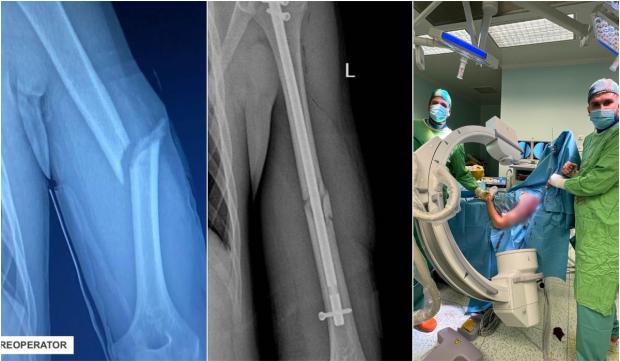

Un pacient în vârstă de 16 ani s-a prezentat la Spitalul Clinic Județean de Urgență Bihor cu o fractură diafiză humerală cu deplasare, în urma unui accident rutier.

Osul lung al brațului (humerusul) era fracturat, iar cele două segmente erau deplasate de la locul lor. Adolescentul trebuia operat pentru repunerea la loc a fragmentelor osoase fracturate, soluțiile clasice pentru tratamentul ortopedic al fracturilor pediatrice implicând fie montarea unei plăci cu șuruburi, sau utilizarea tijelor elastice.

Așadar, echipa operatorie a decis să efectueze, în premieră județeană, reducerea ortopedică închisă cu osteosinteză prin tijă zăvorâtă din titan pentru un pacient pediatric. Sub control radiologic, s-a efectuat reducerea ortopedică închisă a osului fracturat, iar apoi s-a introdus o tijă de titan pentru fixarea fragmentelor osoase.

Acest abord a presupus efectuarea de radiografii repetate în timpul intervenției pentru a se vedea unde este tija și cât de aproape este de focarul de fractură. După poziționarea acesteia pe os, următorul pas a fost montarea a 3 șuruburi pentru ancorarea tijei în humerus. Tija de titan este de calibrul canalului medular, având dimensiuni de 28 cm lungime 8 phi în diametru. Intervenția a fost una de complexitate ridicată, humerusul fiind un os foarte greu de redus. Operația a avut loc în data de 20.04.2024, a durat o oră și jumătate și a decurs bine", anunţă spitaljudetean-oradea.ro